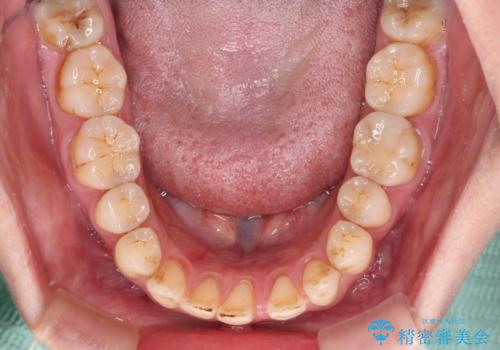

- 上下前歯の隙間を気にして来院された患者様です。

下顎前歯が1本欠損しており、上下小臼歯はクロスバイトとなり、上下前歯の接触もないという不正咬合の状態でした。

クロスバイトはワイヤー矯正が得意とするところであり、上下前歯の非接触や開咬はインビザラインの得意とするところであるので、ワイヤー装置により事前にクロスバイトを改善し、その後にインビザラインにて仕上げていくこととしました。